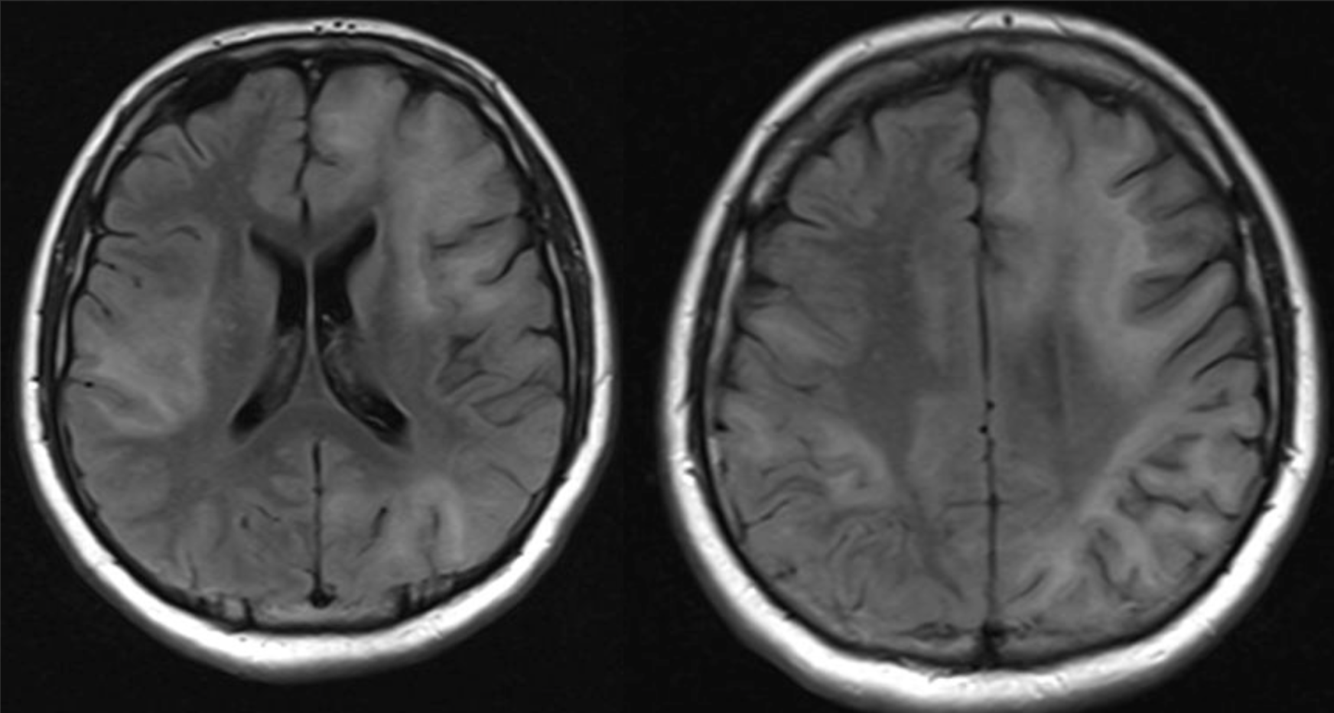

A 45 year-old man with untreated HIV infection presented with 4 months of cognitive slowing.

HIV dementia

Imaging